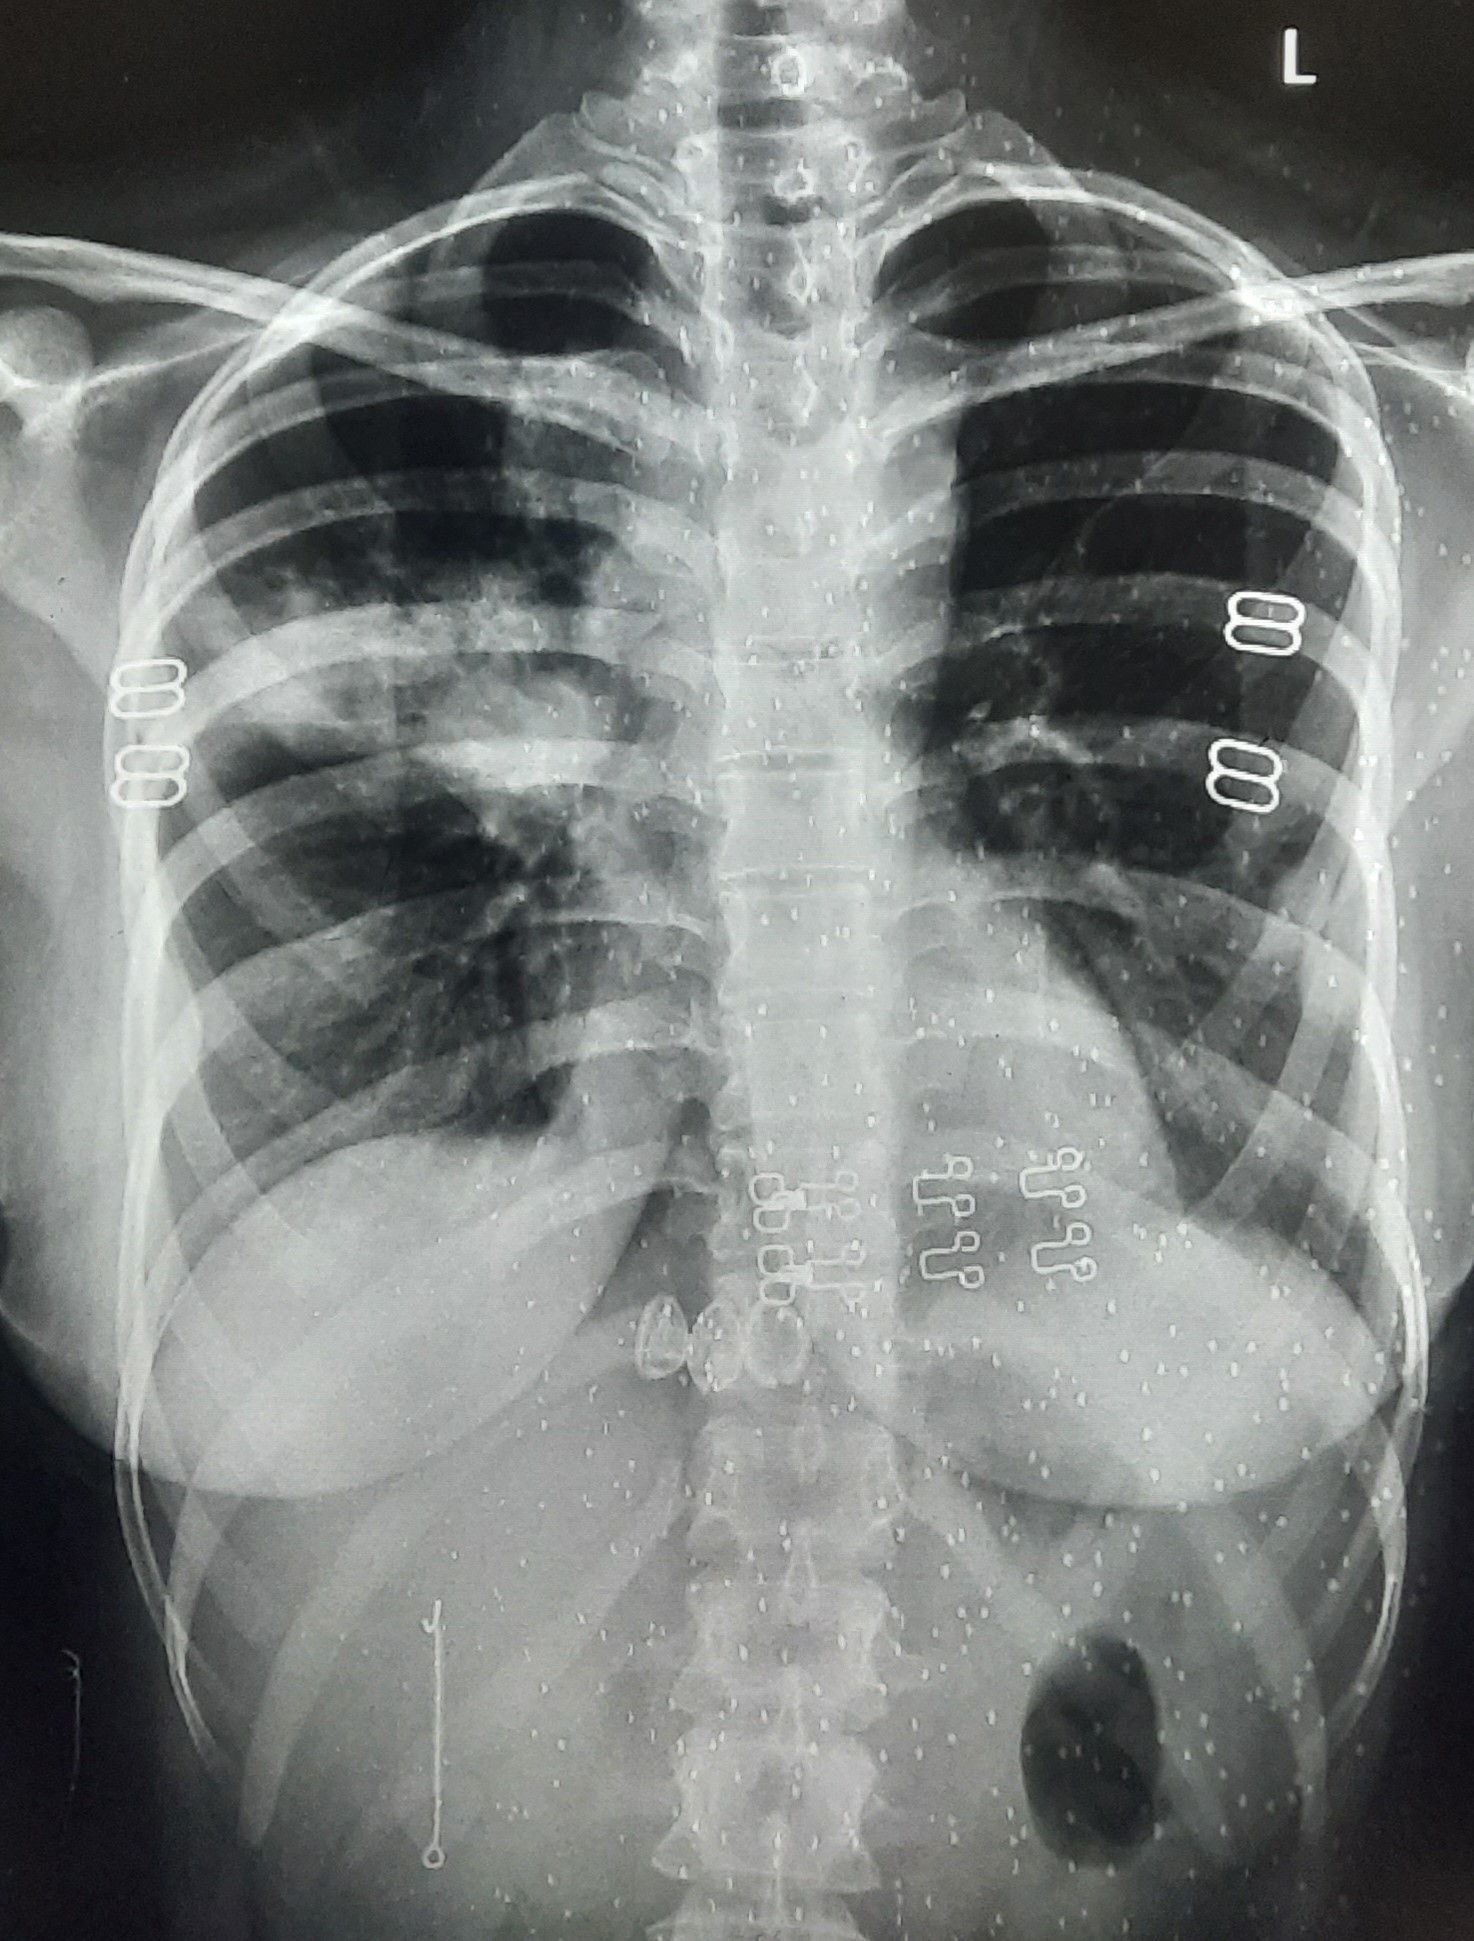

| 297 | IGGMC, Nagpur, Nagpur | P2 | 29-4175 | Sabina Parveen | Consent taken on Paper | 23 Yrs. |

Provisional Diag : PTB Reactivation

Final Diag : ? |

TB Case (Confirmed) | Bilateral Middle Lower Zone Pulmonary TB | Abnormality visible on x-ray |